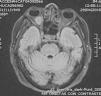

Clinical ObservationThe patient was a 65-year-old woman with no medical history of interest. She had been diagnosed 5 years earlier with sarcoidosis, showing hilar lymph node involvement, with granulomata in the transbronchial biopsy, and had received small doses of steroids. Four years later, she presented with pulmonary progression (chest radiography, high-resolution computed tomography), with normal respiratory function tests, and received no treatment. One year later, she developed right eye pain, intermittent diplopia and asthenia. The ocular fundus, lumbar puncture and general examination were normal, except for a small change in left supraclavicular lymph node. Magnetic resonance imaging revealed a lesion measuring 11mm×17mm×16mm, with well-defined borders, dependent of the optic nerve, did not infiltrate muscle tissue and attracted gadolinium. There was another lesion of less than 1cm in left masticatory space with the same characteristics (Fig. 1). Thoracoabdominal pelvic computed tomography discovered enlarged multiple mediastinal lymph nodes and iliac chains, and 18F-fluorodeoxyglucose-positron emission tomography/computed tomography (PET/CT) showed hypermetabolic lesions at the eye level, the left masticator space, and sacral and thoracic vertebral lymph node involvement. A biopsy of the supraclavicular lymph node demonstrated a diffuse large B cell lymphoma with a post-germinal center immunophenotype. Cytometry recognized an associated T lymphoid population that expressed CD3+, CD5+, CD8+, CD4− and a high index of proliferation (Ki67). Using B- and T-cell rearrangement studies, we confirmed a monoclonal B population. Although a biopsy of the iliac crest gave no sign of lymphoma, we did find evidence with granulomatous infiltration with multinucleated giant cells.

DiscussionOur patient with sarcoidosis developed a retroocular mass, with a radiological differential diagnosis of sarcoidosis vs lymphoma. In sarcoidosis, thoracic lymph node involvement is characteristic and, although, it can also appear in other territories, it does so in fewer than 50% of the cases. As it is a systemic disease, in at least 10% of the patients it can also affect the central nervous system, generally, as leptomeningitis with infiltrations of the basal cisterns of the optic chiasm region and the hypothalamic-pituitary-adrenal axis. In these cases, it is essential to rule out infections and neoplasms, although magnetic resonance imaging or PET/CT confirm the diagnosis.2 In our patient, the diagnosis could be reached after biopsy of a supraclavicular lymph node. Despite presenting bone metabolic activity in PET/CT that suggested lymphomatous infiltration, it was found to be related to sarcoidosis.